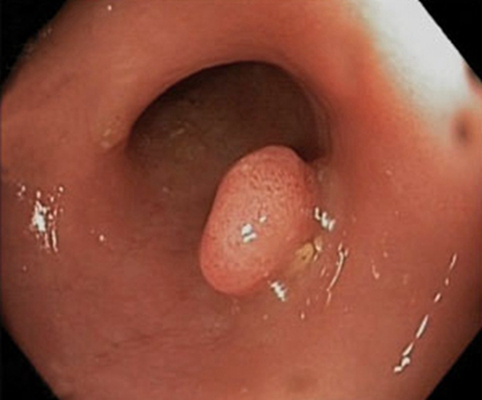

肛門癌圖片

肛癌早期症狀

A:肛門癌的病理類型以鱗狀上皮細胞癌為多見。肛門癌的病變多為突出皮面的結節樣的病變,觸摸時結節表面凹凸不平,多呈不規則形或者菜花樣,質地硬。結節的表面多有潰瘍性的改變,觸之易出血。結節與周圍組織分界不清楚,腫物的活動度差,常常難以推動。觸摸腫塊……